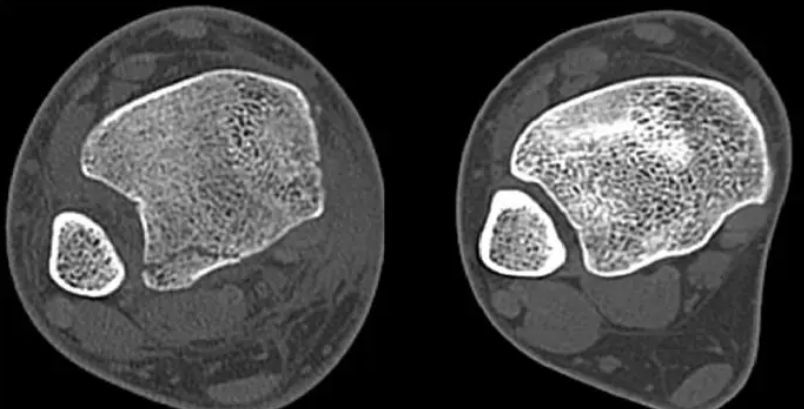

踝關節(jie)損(sun)傷(shang)后,在臨床(chuang)檢(jian)查的基(ji)礎(chu)上(shang),應行常(chang)規X線檢(jian)查,在前(qian)后位X線片(pian)上(shang)脛骨遠端關節(jie)面上(shang)1cm水平,下脛腓(fei)間隙>5mm或脛腓(fei)重疊在前(qian)后位X線片(pian)上(shang)<10mm,表明存(cun)在下脛腓(fei)聯(lian)合損(sun)傷(shang)。